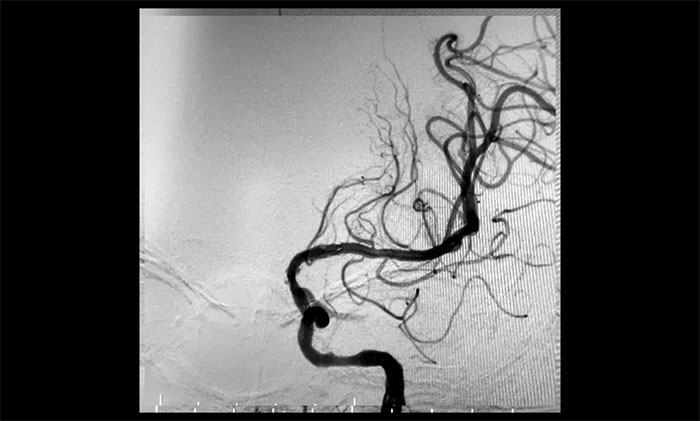

患者为老年男性,因言语不利,伴右侧肢体活动不利入院。外院行头颅CT检查:双侧脑室旁及基底节区腔隙灶。入院后,头颅MRI平扫+DWI+MRA提示,脑干、双侧小脑及双侧大脑半球多发腔梗、缺血灶;MRA:脑动脉硬化,左侧颈内动脉不完全闭塞,右侧颈内动脉C3-C6段、右侧大脑中动脉M2段多发狭窄。“主动脉弓+全脑动脉造影”提示:右颈内动脉起始段重度狭窄,左颈内动脉起始段重度狭窄,串联左颈内动脉岩骨段中度狭窄,左颈内动脉眼动脉段闭塞。

▲ 左颈内动脉起始段重度狭窄,并串联多处狭窄、闭塞

术后一个月,经过综合治疗,患者病情稳定。10月11日,再次行经皮左侧颈动脉慢性闭塞开通术,脑保护伞下左侧颈动脉支架置入手术,经皮左侧颈动脉球囊扩张成形术。术中造影显示,左颈内动脉起始段多发重度狭窄,左颈内动脉前向血流慢,左颈内动脉岩骨段中度狭窄,左颈内动脉眼动脉段、后交通段多发重度狭窄伴次全闭塞。

经微导丝成功进入狭窄、闭塞颈内动脉,在支架保护下,进行球囊逐段扩张,支架置入……,经多次球囊扩张,置入支架后,造影显示左颈内动脉起始段狭窄明显改善,左颈内动脉颅内段顺利再通,左颈内动脉眼动脉段、后交通段狭窄明显改善。造影及3D造影见左颈总动脉、左颈内动脉、左大脑中动脉显影可,行支架CT见颅内支架成形可,手术取得成功!

▲术后,左颈内动脉起始段狭窄明显改善,左颈内动脉颅内段顺利再通,左颈内动脉眼动脉段、后交通段狭窄明显改善